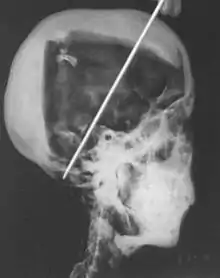

1968 x-rays

In 1968 R. G. Harrison, a professor of anatomy, used a portable x-ray machine to re-examine the mummy of Tutankhamun. Harrison quickly discovered that Carter had dismembered the mummy, something that is not mentioned in his publication. The mummy, surrounded by cotton wool and secured by modern bandages, had deteriorated since last photographed by Carter's team in 1926. The beaded skull-cap had disappeared, as had most of the skin on the head; the eyes appeared to be wide open, and the ears were largely destroyed. The beaded collar was gone, as was the front wall of the king's chest; stray beads from this necklace were seen scattered in the torso on the x-rays. The limbs had been moved and further disarticulated, with the left hand and thumb of the right hand found in the sand under the body.[80][81] Although not mentioned by Harrison, the king's penis was also missing.[81] The additional damage to the mummy and the removal of the skullcap and collar likely occurred during World War II,[60] and components suggested to be from the collar have since appeared on the antiquities market.[82]

The x-rays revealed two levels of resin inside the skull. One was introduced when the body was lying on its back, pooling at the back of the head; the other when the head was tilted far back, settling at the top of the skull. Also present in the skull cavity were small bone fragments which Harrison initially believed to be the result of the embalming process. The fact that skull fragments were discovered led many to assume the king was murdered by a blow to the head, but the X-ray could not support or discredit this theory. His age at death was again estimated to be around 18, with a projected height in life of 168.9 centimetres (5 ft 6.5 in).[80] Serological analysis undertaken by the same team determined that Tutankhamun and the KV55 mummy had the same blood group, further indicating a familial relationship.[83]